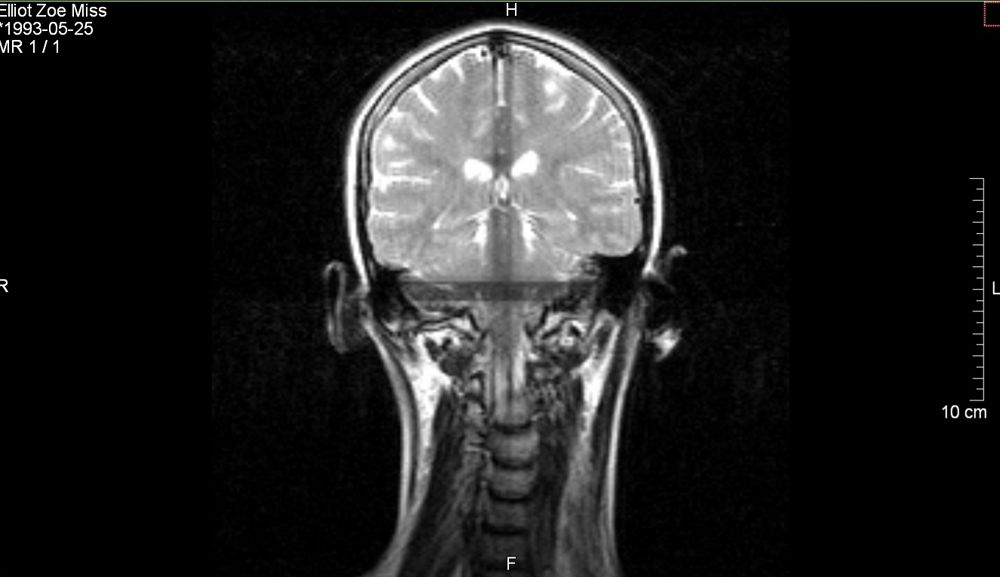

Tests, including a standing MRI scan to monitor the range of movement in her tendons, confirmed that her mobility was actually symptomatic of Ehlers-Danlos Syndrome (EDS), a rare condition affecting the connective tissue.

“Next, I took the little money I had and put it all towards going to London for a private appointment with a specialist in December 2019, who did some tests and officially diagnosed me with CCI and atlantoaxial instability (AAI), meaning both the ligaments and the vertebrae around my neck and spine are unstable."

“They did a scan to see what my neck looked like when I moved around, and everyone was open-mouthed at the results. My head went right back, almost as if it was going to come off."